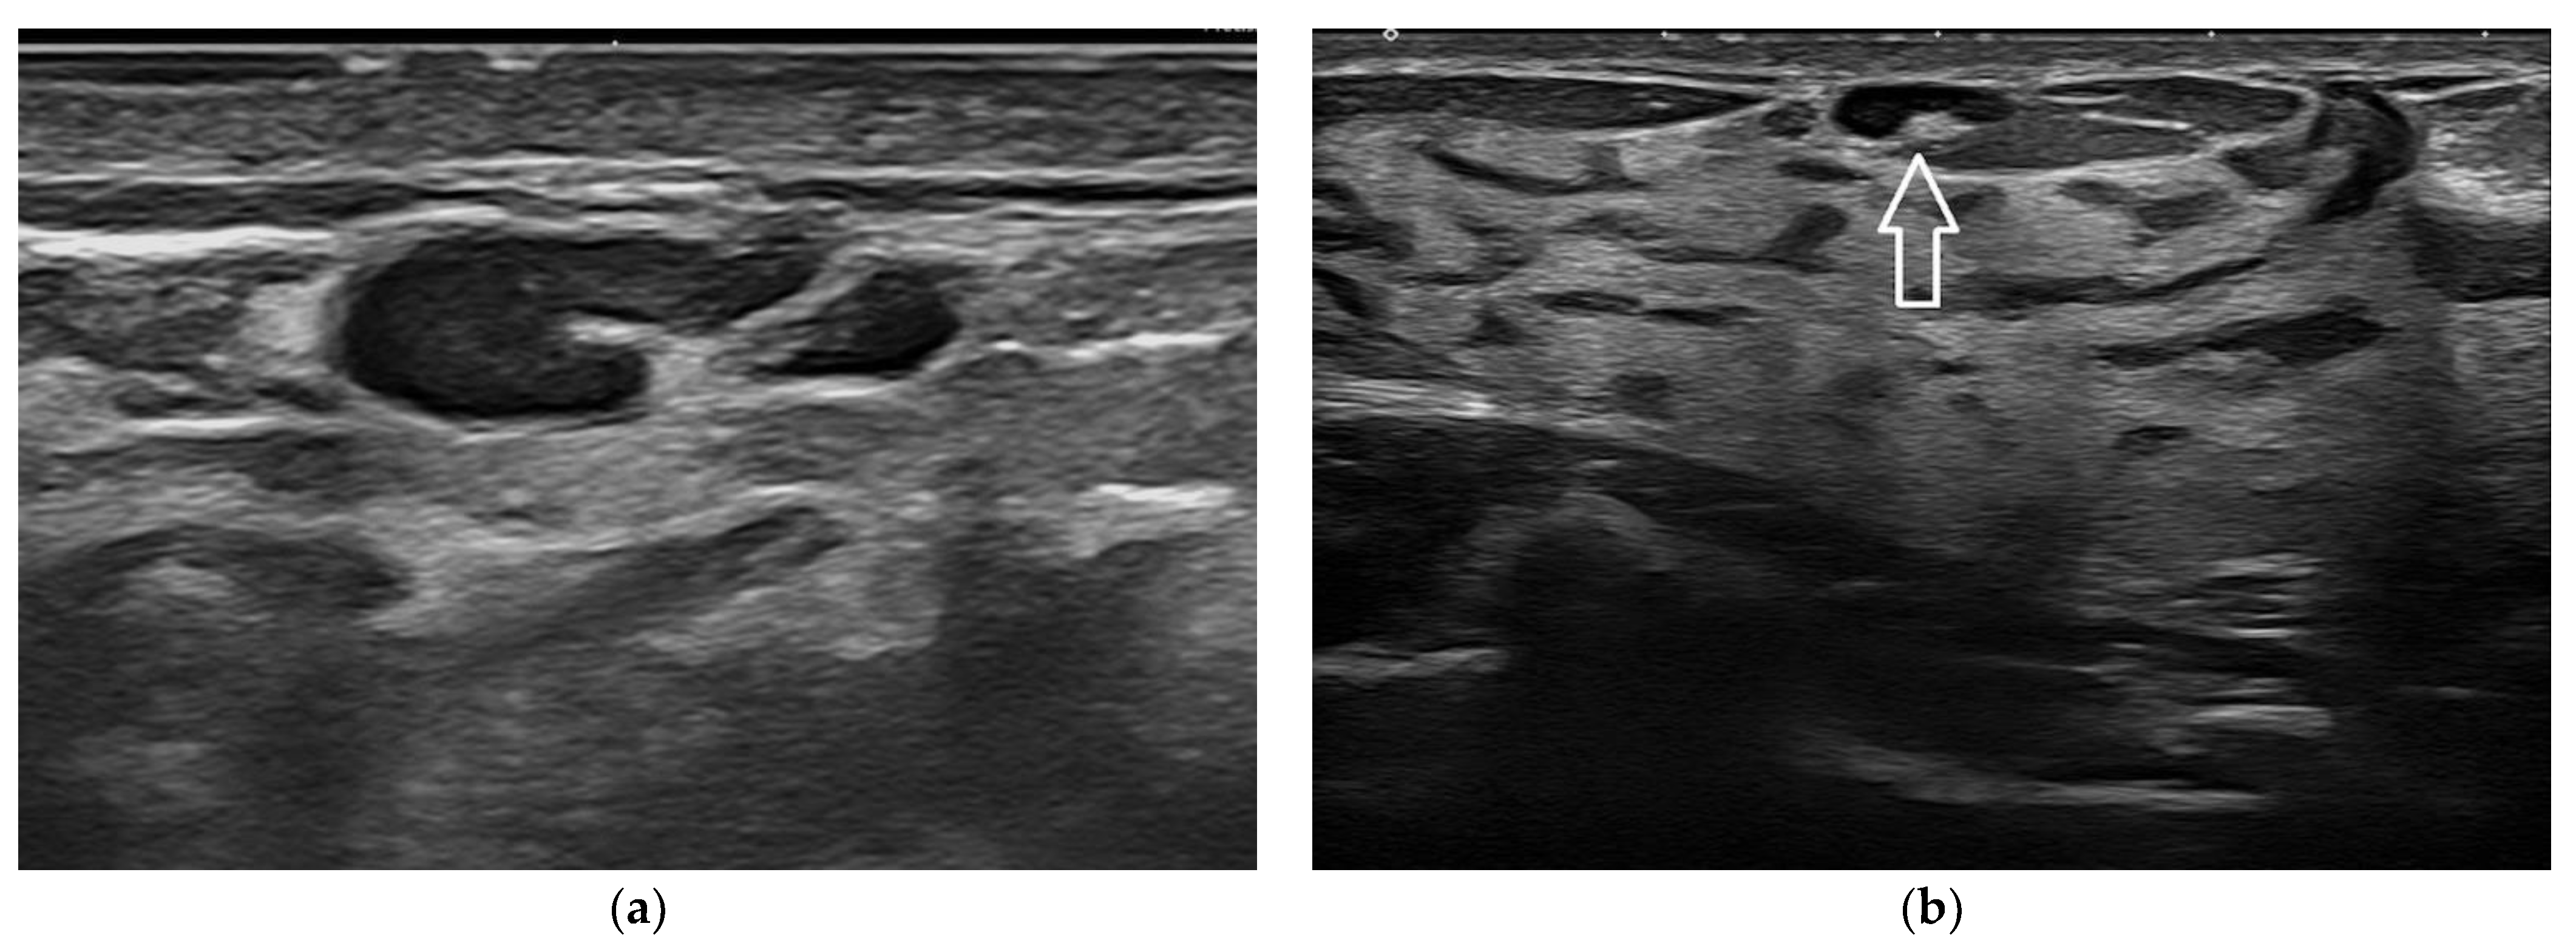

Figure 10. An irregular distortion detected in a patient with a history of breast augmentation surgery and a submuscular implant (a, arrow). The lesion is better displayed at 22 MHz (b), where the spiculated margins, the hyperechoic desmoplastic border, and the internal echoic spots due to microcalcification are better appreciated. Histology confirmed an invasive ductal carcinoma.